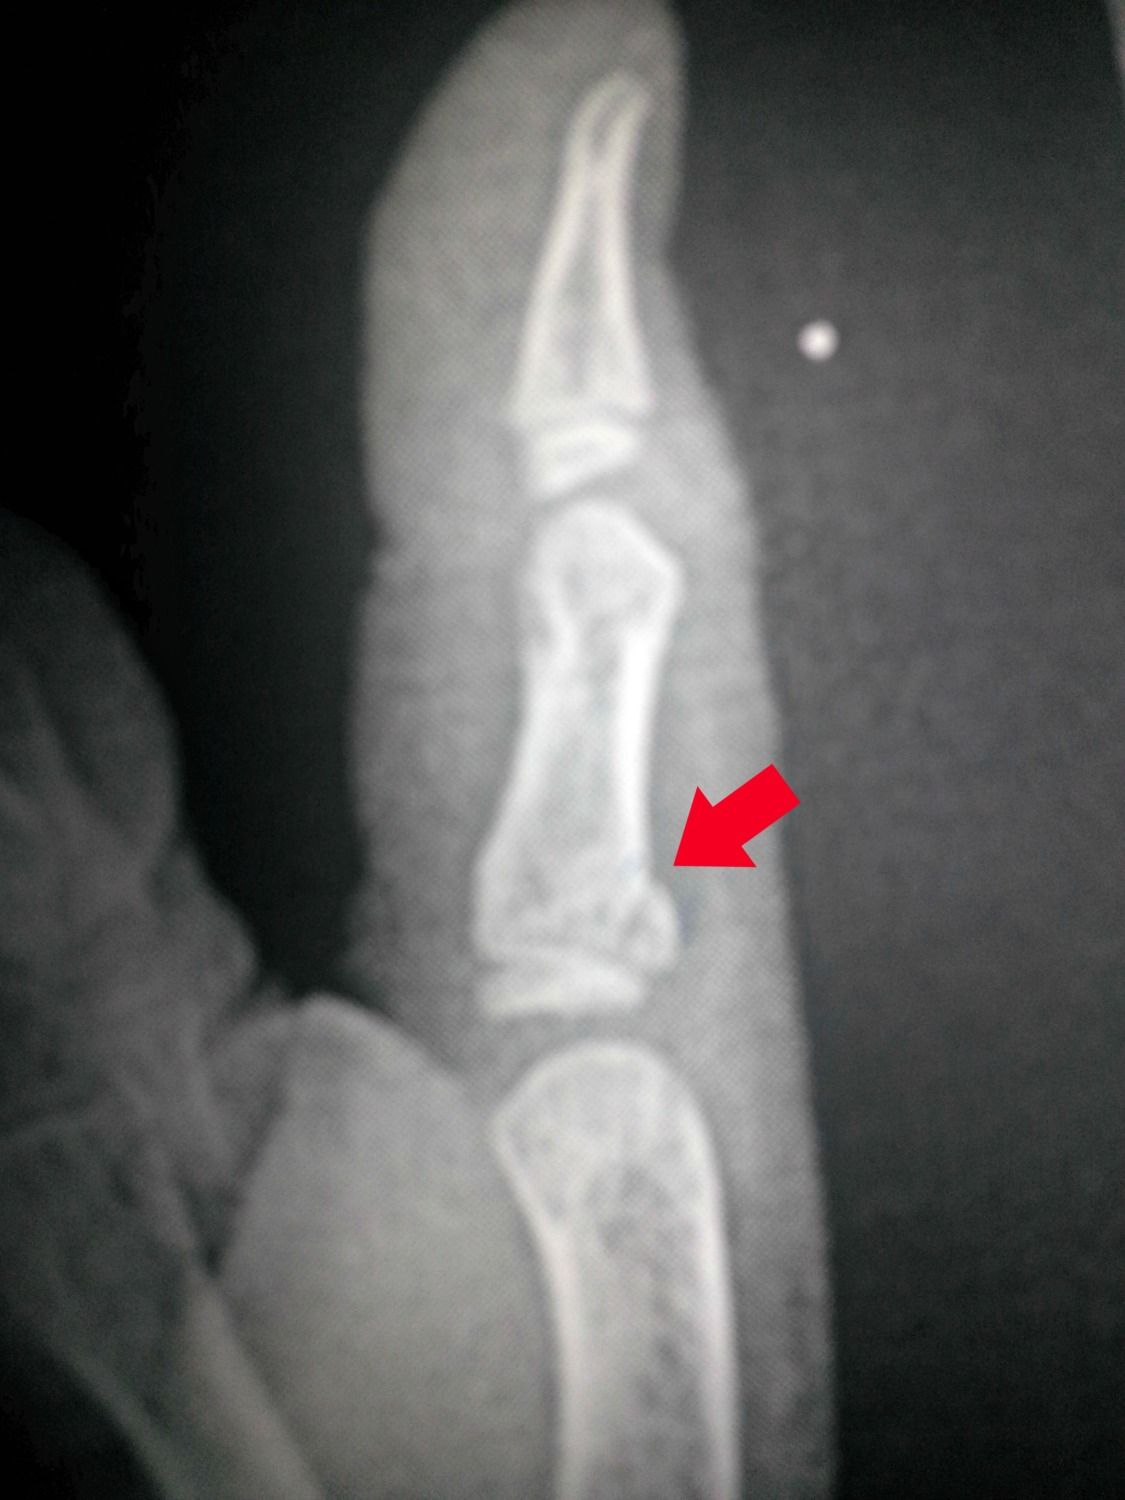

We had a little excitement today.... well, kinda.... Tuesday my son fell and when he caught himself, he hit his thumb. We figured it was just jammed, so had him put ice on it. It was a little sore Tues. night and Wed. but he didn't say anything after that. This morning I was clipping his fingernails, and noticed that his thumb was still swollen and a little bruised. I called his doctor, and they wanted me to take him for xrays. When hubby got home, we went on to the ER. They did the xrays, and we waited for them to get the results, call his doctor and them telling us that his thumb was broken. Since we had waited, and were still there his dr wanted us to go into the ER and have it splinted for the weekend. We have to go to his dr on Monday, and get an appointment for Orthopedics. He will end up in a cast for a few weeks, since it is his thumb, and right next to his hand. I feel awful that his thumb has been broken for 3 days, and we are just now taking him to have it checked.... He has such a high pain tolerance, that he deals with things that most kids would whine and fuss about....